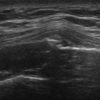

Gãy xương sườn

» Thông tin: Nữ giới – 52 tuổi.

» Lâm sàng: Chấn thương ngực.